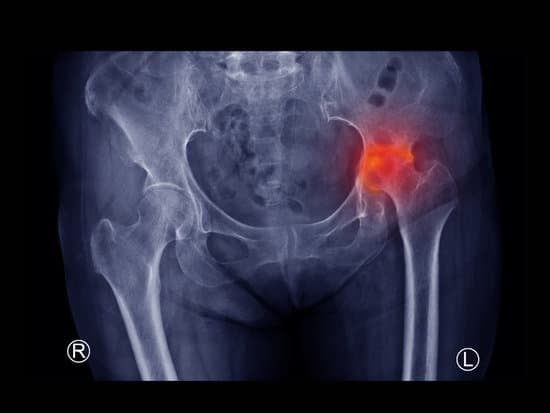

대퇴골두 무혈성 괴사 (Avascular Necrosis)

대퇴골두 무혈성 괴사(Avascular Necrosis, AVN)는 대퇴골의 머리 부분(대퇴골두)으로 가는 혈액 공급이 중단되면서 뼈 조직이 죽어가는 질환입니다.

X-레이: 초기 단계에서는 정상으로 보일 수 있으나, 진행된 단계에서는 뼈의 변형이 나타날 수 있습니다.